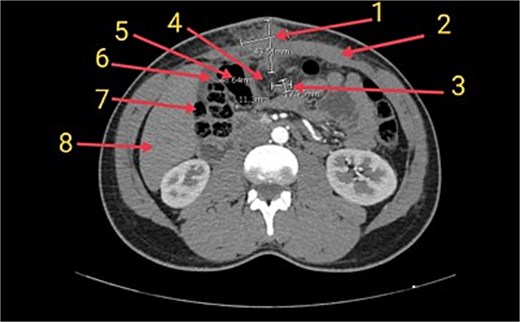

Ultrasonography revealed a heterogeneous supraumbilical lesion extending intramuscularly and into the intra-abdominal cavity, measuring up to 6 cm, with surrounding edema and increased vascularity. MRI demonstrated an ill-defined, heterogeneously enhancing mass measuring approximately 5.2 × 5 cm, with low T1 and intermediate-to-high T2 signal intensity, associated fat stranding, and close proximity to adjacent bowel loops without a clear fat plane. Contrast-enhanced computed tomography (CT) confirmed extension through the rectus sheath with inseparability from the omentum and nearby colon, raising concern for an infiltrative process (Fig. 1).

Axial CT image of the abdomen showing the inflammatory myofibroblastic tumor (1) in the supraumbilical anterior abdominal wall. The mass is closely associated with the rectus sheath (2), a presumed lymph node (3), and the greater omentum (4), which appears inseparable from the tumor. Adjacent bowel loops including the transverse colon (5), hepatic flexure (6), and ascending colon (7) are noted in close proximity. The liver is also partially visible (8) in the field.